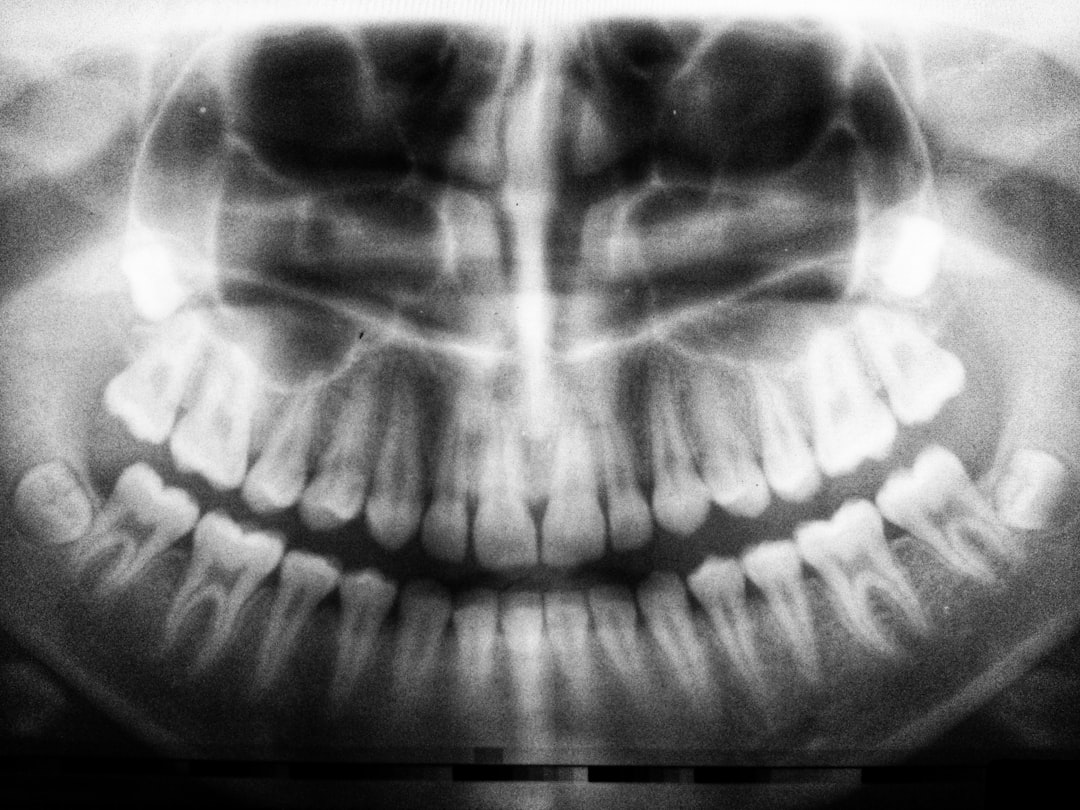

우리의 치아는 단순히 음식을 씹는 기능만을 수행하는 것이 아닙니다. 34번 치아는 우리 몸의 전반적인 건강에 직접적인 영향을 미치는 중요한 역할을 하고 있습니다. 이 치아는 특히 소화 과정에 큰 영향을 주며, 적절하게 관리하지 않을 경우에는 여러 건강 문제를 유발할 수 있습니다. 34번 치아가 상실되거나 손상되면, 여러분은 음식을 제대로 씹지 못할 수도 있고, 이로 인해 영양소 섭취가 줄어들 수 있습니다. 제대로 된 영양소 섭취는 건강을 유지하는 데 필수적입니다. 따라서 34번 치아를 소중히 여기는 것이 얼마나 중요한지를 깨달을 필요가 있습니다.

34번 치아는 소화과정에서 그들이 수행하는 중요한 역할 덕분에 우리의 건강에 밀접하게 연결되어 있습니다. 제대로 씹지 못한 음식은 소화기관에 부담을 주며, 이는 위장 문제를 초래할 수 있습니다. 만약 34번 치아에 문제가 생긴다면, 여러분은 더 자주 소화 불량을 경험할 수 있고, 이는 결국 체중 증가로 이어질 수 있습니다. 어떤 음식을 어떻게 섭취하느냐에 따라 우리의 건강은 크게 달라질 수 있기 때문에 34번 치아가 제 기능을 하는 것이 매우 중요합니다.

뿐만 아니라, 34번 치아가 손상되면 이로 인해 발생하는 염증이나 감염이 인체의 다른 부분에도 영향을 미칠 수 있습니다. 의학적으로 연구 결과에 따르면, 구강 건강은 심혈관 질환이나 당뇨병과도 밀접한 관련이 있습니다. 따라서 34번 치아를 건강하게 유지하는 것은 우리가 질병에 걸릴 위험을 줄이고, 전반적인 건강을 유지하는 데 큰 도움이 됩니다.

34번 치아가 건강에 영향을 미치는 방식은 단순히 치아 자체의 문제가 아닙니다. 구강 건강은 우리의 전반적인 건강과 연결되어 있으며, 34번 치아의 건강 관리가 여러 질병을 예방할 수 있습니다. 실제로 심혈관 질환이나 만성염증과 같은 심각한 건강 문제들은 구강 내에서 시작되는 경우가 많습니다. 따라서 예방적 차원에서 정기적인 관리가 필수적입니다.